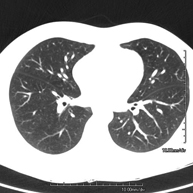

- TC Tórax

Prueba diagnóstica que consiste en obtener imágenes del tórax de alta definición anatómica (pulmones, corazón, mediastino, grandes vasos, caja torácica, etc.) mediante el empleo de un equipo de TC (Tomografía Computarizada). Dichas imágenes se estudian posteriormente en una estación de trabajo que permite reconstrucciones bidimendionales en diferentes planos del espacio y también reconstrucciones 3D (volumétricas). Algunos estudios requieren el empleo de contraste yodado para mejorar la definición de las imágenes.

- TC Tórax alta resolución

Prueba diagnóstica que consiste en el estudio del pulmón mediante el empleo de un equipo de TC (Tomografía Computarizada) obteniendo imágenes bi y tridimensionales que permiten un estudio anatómico altamente específico del pulmón, pudiendo valorar estructuras anatómicas de tamaño muy pequeño. Es una técnica muy importante en el estudio de los pacientes con sospecha de enfermedad pulmonar.